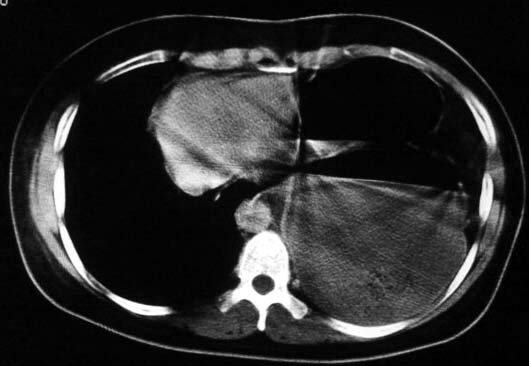

标题: CT5517:女性、24岁,反复胸痛、气促不能平卧半月。 [打印本页]

标题: CT5517:女性、24岁,反复胸痛、气促不能平卧半月。

左肺可见二个含气或液气的囊状影,左肺段支气管、左肺动脉显示不清,纵隔右移,考虑:左肺支气管肺囊肿,左肺发育不良,纵隔疝。

左侧气液腔与胃腔影相连,考虑膈疝。钡餐检查有助于诊断。

我看这是膈疝,在纵隔窗第六\\七幅图像上可见胃粘膜影,再者可见两个腔影,这在液气胸是不会有的.

支持膈疝,纵隔窗内可见消化道的内容物。

“反复胸痛、气促不能平卧半月”。+影像学表现=膈疝